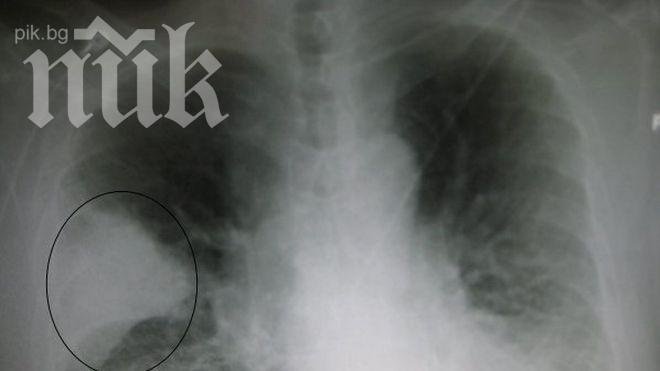

Международният ден за борба с пневмонията се отбелязва всяка година на 12 ноември от 2009 насам, за да повиши информираността относно пневмонията, да допринесе за интервенции, които да защитават срещу и лекуват болестта и да ни обедини за борбата с пневмонията.

Пневмонията е най-сериозният причинител на смърт сред деца под пет годишна възраст, както и водеща инфекциозна причина за детска смъртност по света. Болестта е отнела живота на 1,1 милиона деца през 2012, което е около 17 процента от всички смъртни случаи на деца под пет години, пише "Новинар".

Иновациите в диагностиката и лечението на пневмонията са ключови за предотвратяване на детската смъртност, и най-вече за тези деца, които е най-трудно да бъдат достигнати. Например, изключително важно е да се намери нов метод за ранна диагностика на пневмонията в здравните заведения, където рентгените и лабораторните тестове не са налични или са недостатъчни.